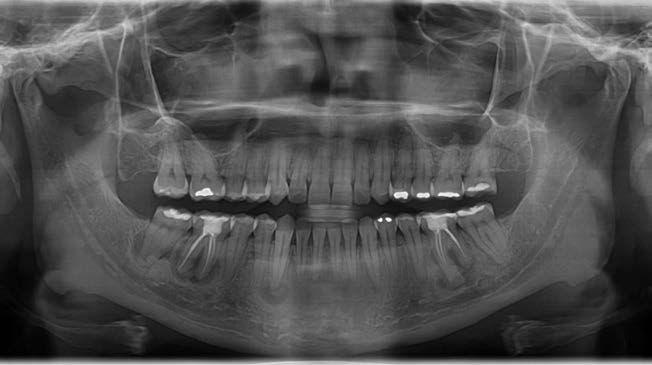

En la radiografía panorámica de 2021 (Figura 2) se evidenciaba una progresión significativa de la lesión, caracterizada por un aumento en la aposición de material radiodenso, especialmente en el cuarto cuadrante. La paciente permanecía asintomática en el momento de la evaluación. Se estableció el diagnóstico de DCOF y se optó por una conducta terapéutica expectante, con controles periódicos cada 6 meses.